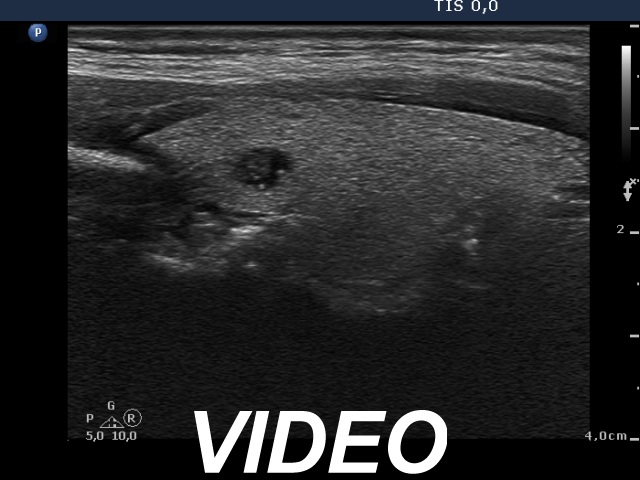

Clinical presentation: A 57-year-old woman was referred for evaluation of a hyperparathyroidism and elevated serum calcium level.

Laboratory tests: TSH 3.70 mIU/L, calcium 3.08 mM/L, phosphorus 0.67 mM/l, parathormone 177.4 pg/mL (normal value: 15-66).

Ultrasonography: The thyroid was echonormal. There was a small hypoechogenic lesion in the upper central part of the right lobe. The lesion presented hyperechogenic granules. We could not find any discrete abnormalities outside the thyroid.

Aspiration cytology of the lesion resulted in benign lesion which might correspond either to a parathyroid adenoma or a benign thyroid lesion.

Wash-out thyroglobulin was low (9.08 mg/L), while wash-out parathormone resulted in 203 pg/mL. Serum thyroglobulin was 9.84 mg/L.

Our final diagnosis was parathyroid adenoma.